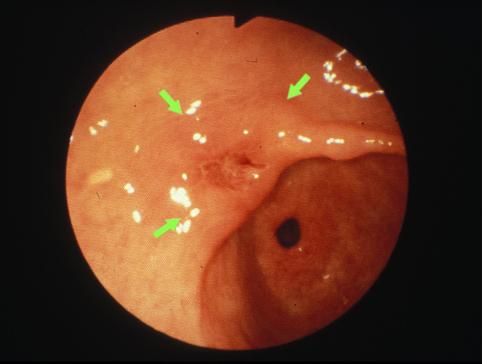

疾病(病理主体)的分类恶性上皮性肿瘤/腺癌

部位(按器官分)胃(部位)/前庭

检查方法内窥镜

肿瘤的肉眼分类0型(表在型)/IIa型(IIa+IIc)

肿瘤最大直径20~24

肿瘤的深度sm